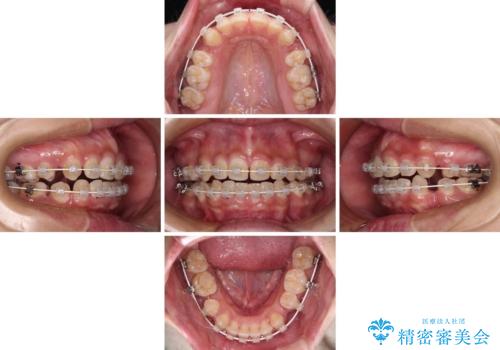

- 矯正装置

- 審美装置

- 治療期間

- 1年11ヶ月

通常は上下左右の第一小臼歯4本を抜歯することになりますが、右側臼歯部の咬合が上顎前突気味であったため、下顎右側のみ第二小臼歯を抜歯し、ワイヤー装置にて矯正治療を行うこととしました。